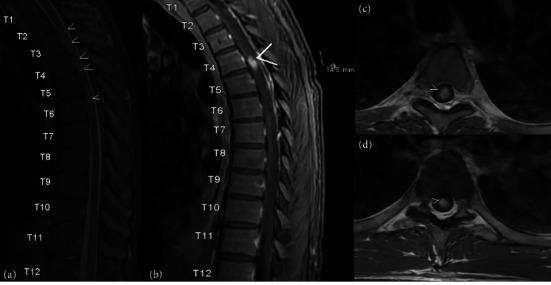

Histoplasmosis is a fungal infection caused by the fungus that can rarely present with central nervous system (CNS) manifestations that include meningitis, encephalitis, focal brain or spinal cord lesions, and stroke syndromes. Because of this variation from patient to patient, CNS histoplasmosis is a difficult clinical diagnosis to make, which can be further hindered by no highly sensitive diagnostic testing available. Here, we present a unique case of a 46-year-old male immunocompromised due to type 1 diabetes mellitus with disseminated histoplasmosis as an acute presentation of myelopathy. Patient had left leg weakness for a few days prior to presentation and a neurological exam remarkable for signs of acute thoracic myelopathy, specifically concerning for Brown-Séquard syndrome. MRI imaging demonstrated an enhancing thoracic spinal cord lesion along with multiple cerebral enhancing lesions, bilateral adrenal masses, and innumerable pulmonary nodules. Biopsy results demonstrated yeast forms consistent with Histoplasma species.

组织胞浆菌病是一种由真菌引起的真菌感染,很少会出现中枢神经系统(CNS)表现,包括脑膜炎、脑炎、局灶性脑或脊髓病变以及中风综合征。由于患者之间存在这种差异,中枢神经系统组织胞浆菌病的临床诊断很困难,而且目前没有高度敏感的诊断测试,这可能会进一步阻碍诊断。在此,我们报告一例独特病例,一名46岁男性因1型糖尿病免疫功能低下,以播散性组织胞浆菌病作为脊髓病的急性表现。患者在就诊前几天出现左腿无力,神经系统检查显示有急性胸段脊髓病的体征,尤其符合布朗 - 塞卡尔综合征。MRI成像显示胸段脊髓有强化病变,同时还有多个脑部强化病变、双侧肾上腺肿块以及无数肺部结节。活检结果显示酵母形态与组织胞浆菌属一致。